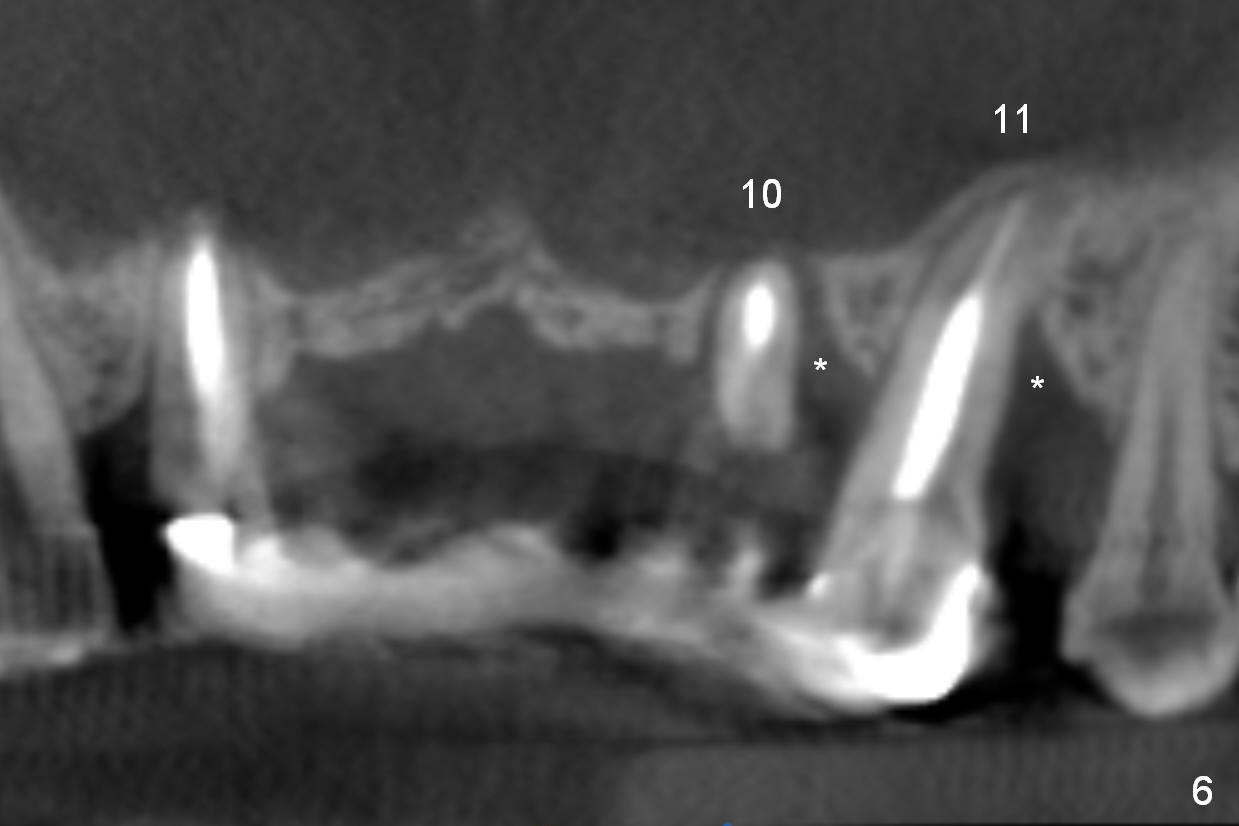

A 53-year-old man chips porcelain of the upper anterior bridge after implant placement at #14 and 15. Since he will return to home country for visit in the next few months, he is eager to restore the anterior restoration. Two of the abutments (#10, 11) appear to have severe bone loos (Fig.1,2 *). It does not seem to be a ideal treatment plan to redo the bridge. The edentulous ridge is atrophic at #8 and 9. It appears that 2.5 mm 1-piece implants (Fig.3,4) fit better than 3.0 mm one (Fig.2). There is a buccal concavity at #9 (Fig.1 red dashed line). The 2.5 mm implant at #9 should be placed between the Incisive Canal (Fig.1 I) and the buccal concavity (Fig.4). The ridge at the buccal concavity is not suitable for implant placement (Fig.5). The palatal plate (Fig.2 P) is usually denser and thicker than the buccal one. The osteotomy for the implant is initiated palatally; the implant is placed below the buccal crest (Fig.2 >). The exposed lingual thread will be covered by bone graft (Fig.3 pink circles) and collagen dressing. Since the ridge at #9 appears more atrophic, a 2.0 mm 1-piece implant may be indicated. The bridge will be sectioned between 7 and 8 and 9 and 10.